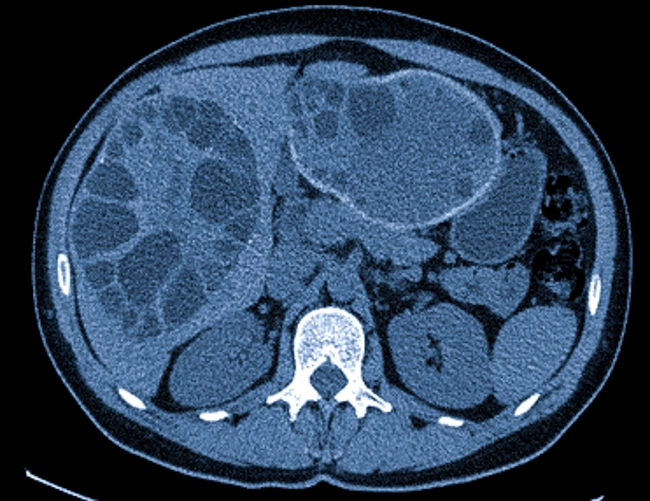

Сахипов Муса Мендыбаевич специализируется на передовых, минимально инвазивных хирургических методах лечения  ожирения, сахарного диабета и метаболического синдрома, хирургических поражений печени, желчных путей и поджелудочной железы, запущенных заболеваний органов брюшной полости, забрюшинного пространства и всего желудочно-кишечного тракта.